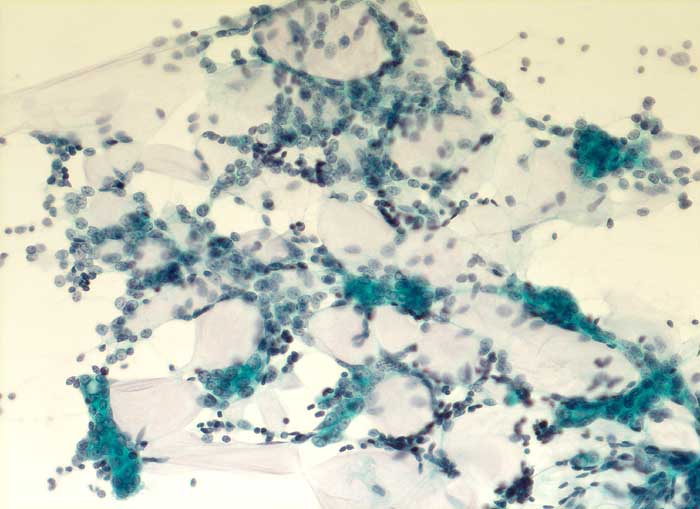

Adenoidzystisches Karzinom

Feinnadelpunktion Mamma: Grosse, zum Teil dreidimensional erscheinende Verbände aus kleinen, ziemlich monomorphen Zellen. Die netzartig verzweigten Verbände umschliessen amorphe mukoide Matrix.

Zytologische Diagnose: Adenoidzystisches Karzinom.

Kommentar: Adenoidzystische Karzinome kommen vor allem im Bereich der Speicheldrüsen vor, treten aber auch in anderen Organen auf. Sie machen weniger als 0.1% - 0.2% der Mammakarzinome aus.